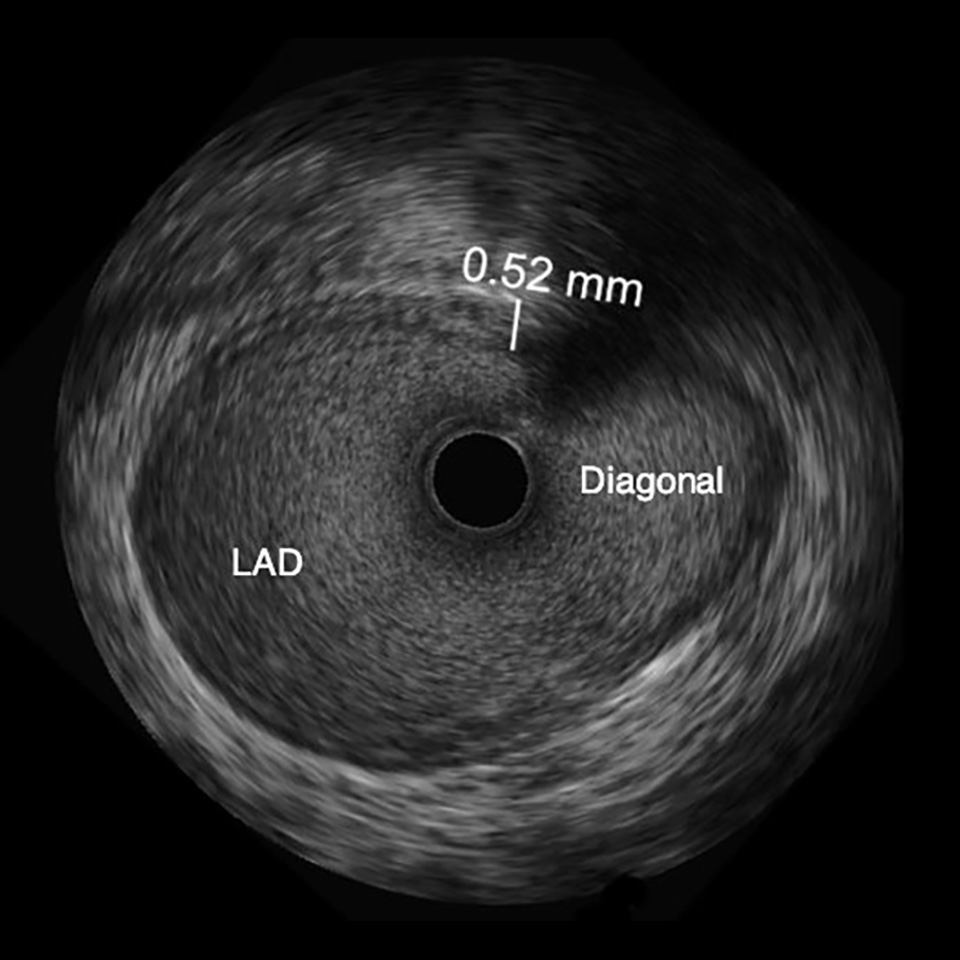

OPTICROSS HD Imaging Catheter 60MHz

IVUS image of inside a coronary vessel using the 60MHz Opticross catheter

Axial resolution: 22µm